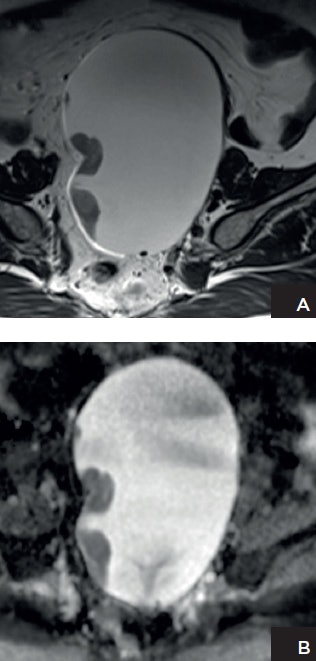

Dr. Evis Sala, PhD, a professor of radiology at Weill Cornell Medicine and chief of the Body Imaging Service at Memorial Sloan Kettering Cancer Center in New York City, intends to show how general radiologists can optimize MRI of the ovaries.

Tailored MRI protocols of around 20 minutes can answer specific clinical questions when adnexal lesions are indeterminate in ultrasound, she explained. Most of these indeterminate lesions that are sent to MRI for characterization will turn out to be benign lesions such as endometriomas and dermoid cysts. In these cases, there is no need for DWI or dynamic contrast-enhanced MRI because anatomical images are sufficient for an accurate diagnosis providing that image resolution is adequate. When evaluating the extent of endometriosis, for example, diffusion or contrast is only needed if there is suspicion of an arising tumor and these images would need to be reviewed before the examination is complete.

One major DWI pitfall is the correct use of restriction information. "No diffusion restriction indicates the presence of a benign lesion. Restricted diffusion is nonspecific. For example, benign lesions such as endometrioma and dermoids can show marked restricted diffusion," she said.